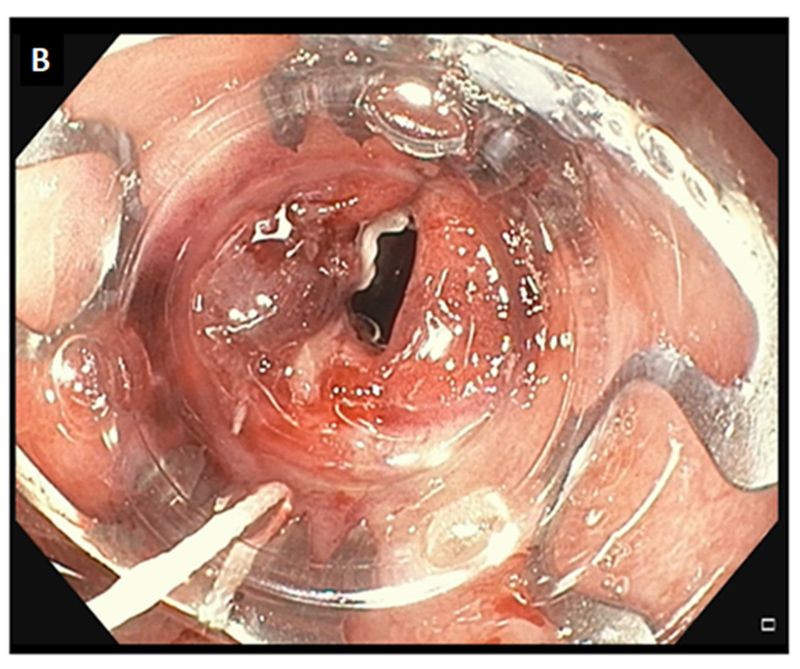

A 57-year-old male with a medical history of diabetes mellitus and morbid obesity underwent a Roux-en-Y gastric bypass surgery. The patient manifested a staple-line anastomotic leakage. After one week of conservative management, a 1.5cm persistent leakage was confirmed both radiologically (Figure A) and endoscopically (Figure B), so an endoscopic closure with over the scope clip (OTSC) using the suction method was performed (Figure C). Leakage of gastric liquids stopped after OTSC closure. No recurrence of the leakage was observed during the 12-month follow-up.